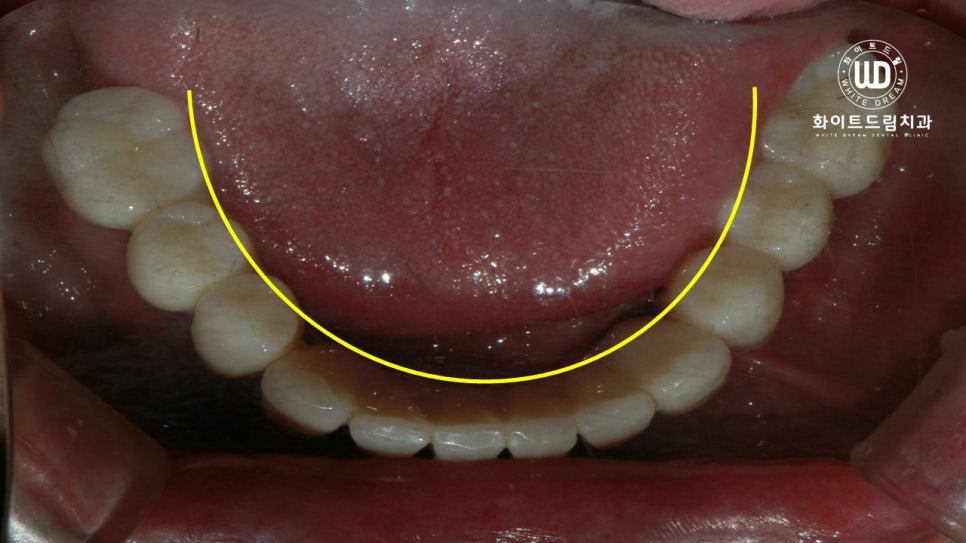

치료가 완료된 사진을 살펴보면 임플란트가 뿌리부터 머리까지 나란히 매끄럽게 연결되어 있는 것을 확인하실 수 있는데, 상악 하악의 U자 형태가 본 케이스와 같이 나올 수 있으려면 임플란트 보철 식립 방향을 잘 체크해야합니다.